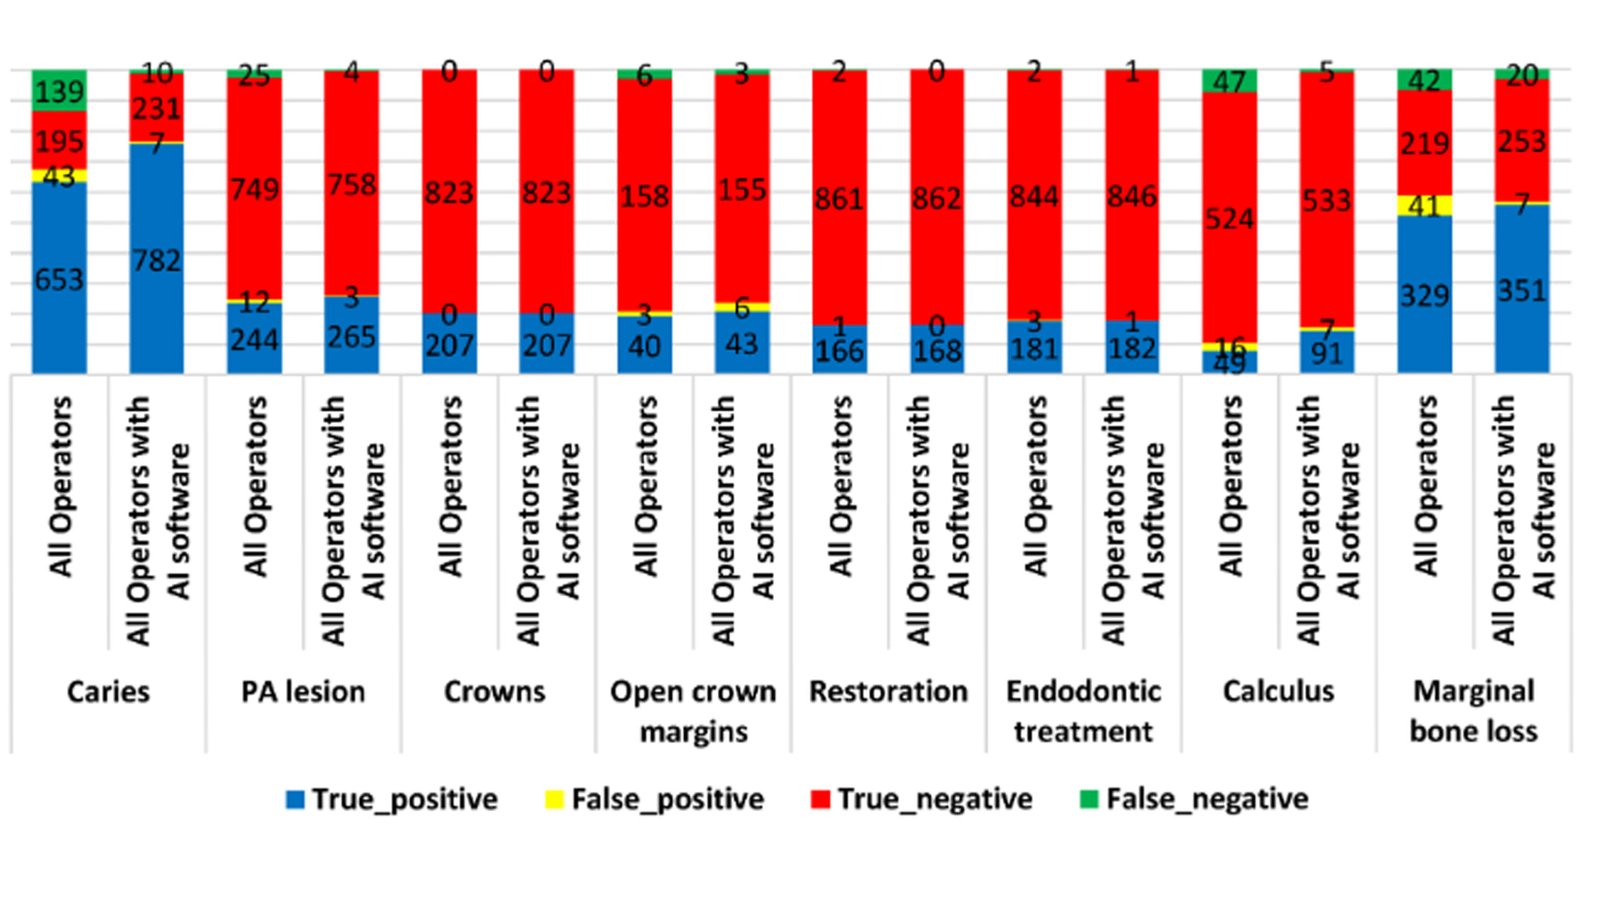

Leveraging AI-driven simulations, this segment integrates predictive modeling with clinical design. We optimize prosthetic, implant, and restorative solutions by forecasting mechanical performance, identifying risk areas, and supporting data-driven treatment planning.